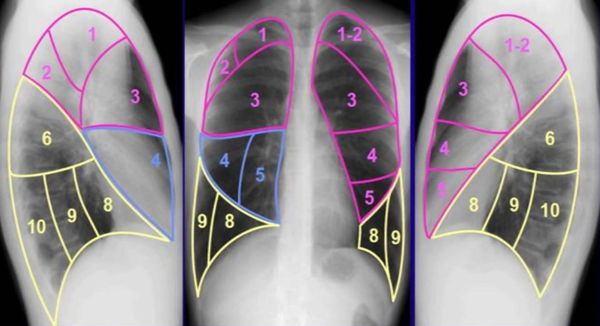

Основной рентгенологический признак при туберкулёме — это фокусное затемнение, чаще расположенное под плеврой в 1, 2 или 6-м сегменте лёгких. Правильная форма затемнения (круглая) характерна для солитарной туберкулёмы, а неправильная форма (овальная) — для конгломератной. Однако при постановке диагноза врачи редко уточняют форму, так как на выбор метода терапии это не влияет. В свою очередь плотность туберкулёмы может косвенно охарактеризовать давность процесса (например, включения кальция говорят об исходе заболевания, т. е. соли кальция замещают казеозные массы).

Сегменты лёгких

Компьютерная томография позволяет исследовать лёгкие более подробно, оценить лимфоузлы и обнаружить «следы» перенесённого туберкулёза. Однако КТ назначают, только когда есть изменения на флюорографии, которые ранее не определялись.